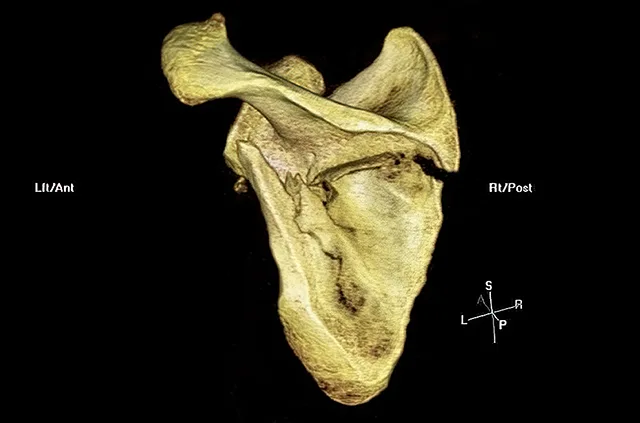

Prelom lopatice

Prelom lopatice je redak jer je ova kost dobro zaštićena grudnim košem i okolnim mišićima. Do preloma lopatice dolazi usled ozbiljnijih trauma prilikom direktnog udarca ili pada na rame (na primer, sa motora ili sa velike visine). Prelomi lopatice često su udruženi sa povredama grudnog koša.

Prelom lopatice, CT rekonstrukcija